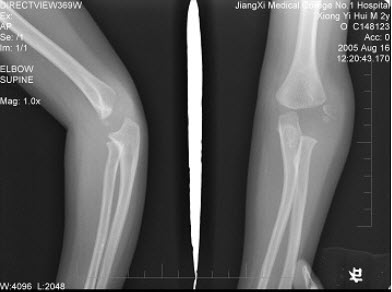

C.躯干